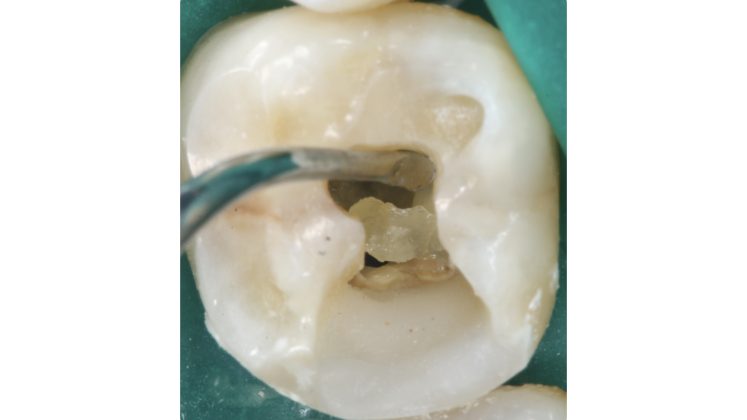

La regola dell'opalescenza e della traslucenza entra in gioco in casi di calcificazioni camerali, situazioni in cui distinguere il pavimento della camera pulpare dalla presenza di residui calcoli può risultare complesso. Iniziare a sondare con strumenti a mano o meccanici un canale prima di aver rimosso tutte le calcificazioni camerali può determinare diversi rischi: complesso inserimento degli strumenti che sarebbero anche sottoposti a un maggiore stress durante la loro attivazione, disseminazione di frammenti all’interno dei canali che potrebbero ostruirsi a diversi livelli.

In aiuto dell’operatore la differente capacità di riflettere la luce (l’utilizzo di una sorgente luminosa assieme al sistema ingrandente agevola molto nella valutazione) del pavimento rispetto al tessuto calcificato risulta un prezioso riferimento.

Il pavimento della camera pulpare si presenta sempre con un aspetto più scuro ed opaco rispetto al tessuto calcificato che tende ad essere lucido con un effetto che potremmo definire “vetrificato” (Figure 15-20).

Talvolta la differenza è evidente, in altri casi molto più sottile e quindi anche le difficoltà incontrate possono essere maggiori.

Non appena vengono identificati gli orifizi canalari la tentazione alla quale resistere è di provare a sondare immediatamente i canali esponendosi ai sopracitati rischi.

Asciugare la camera pulpare è il primo passaggio da compiere per poter visualizzare in modo netto le differenze.

A seguire l’utilizzo alternato di vari dispositivi a secco a bassi giri permette di distaccare ed eliminare i residui calcificati.